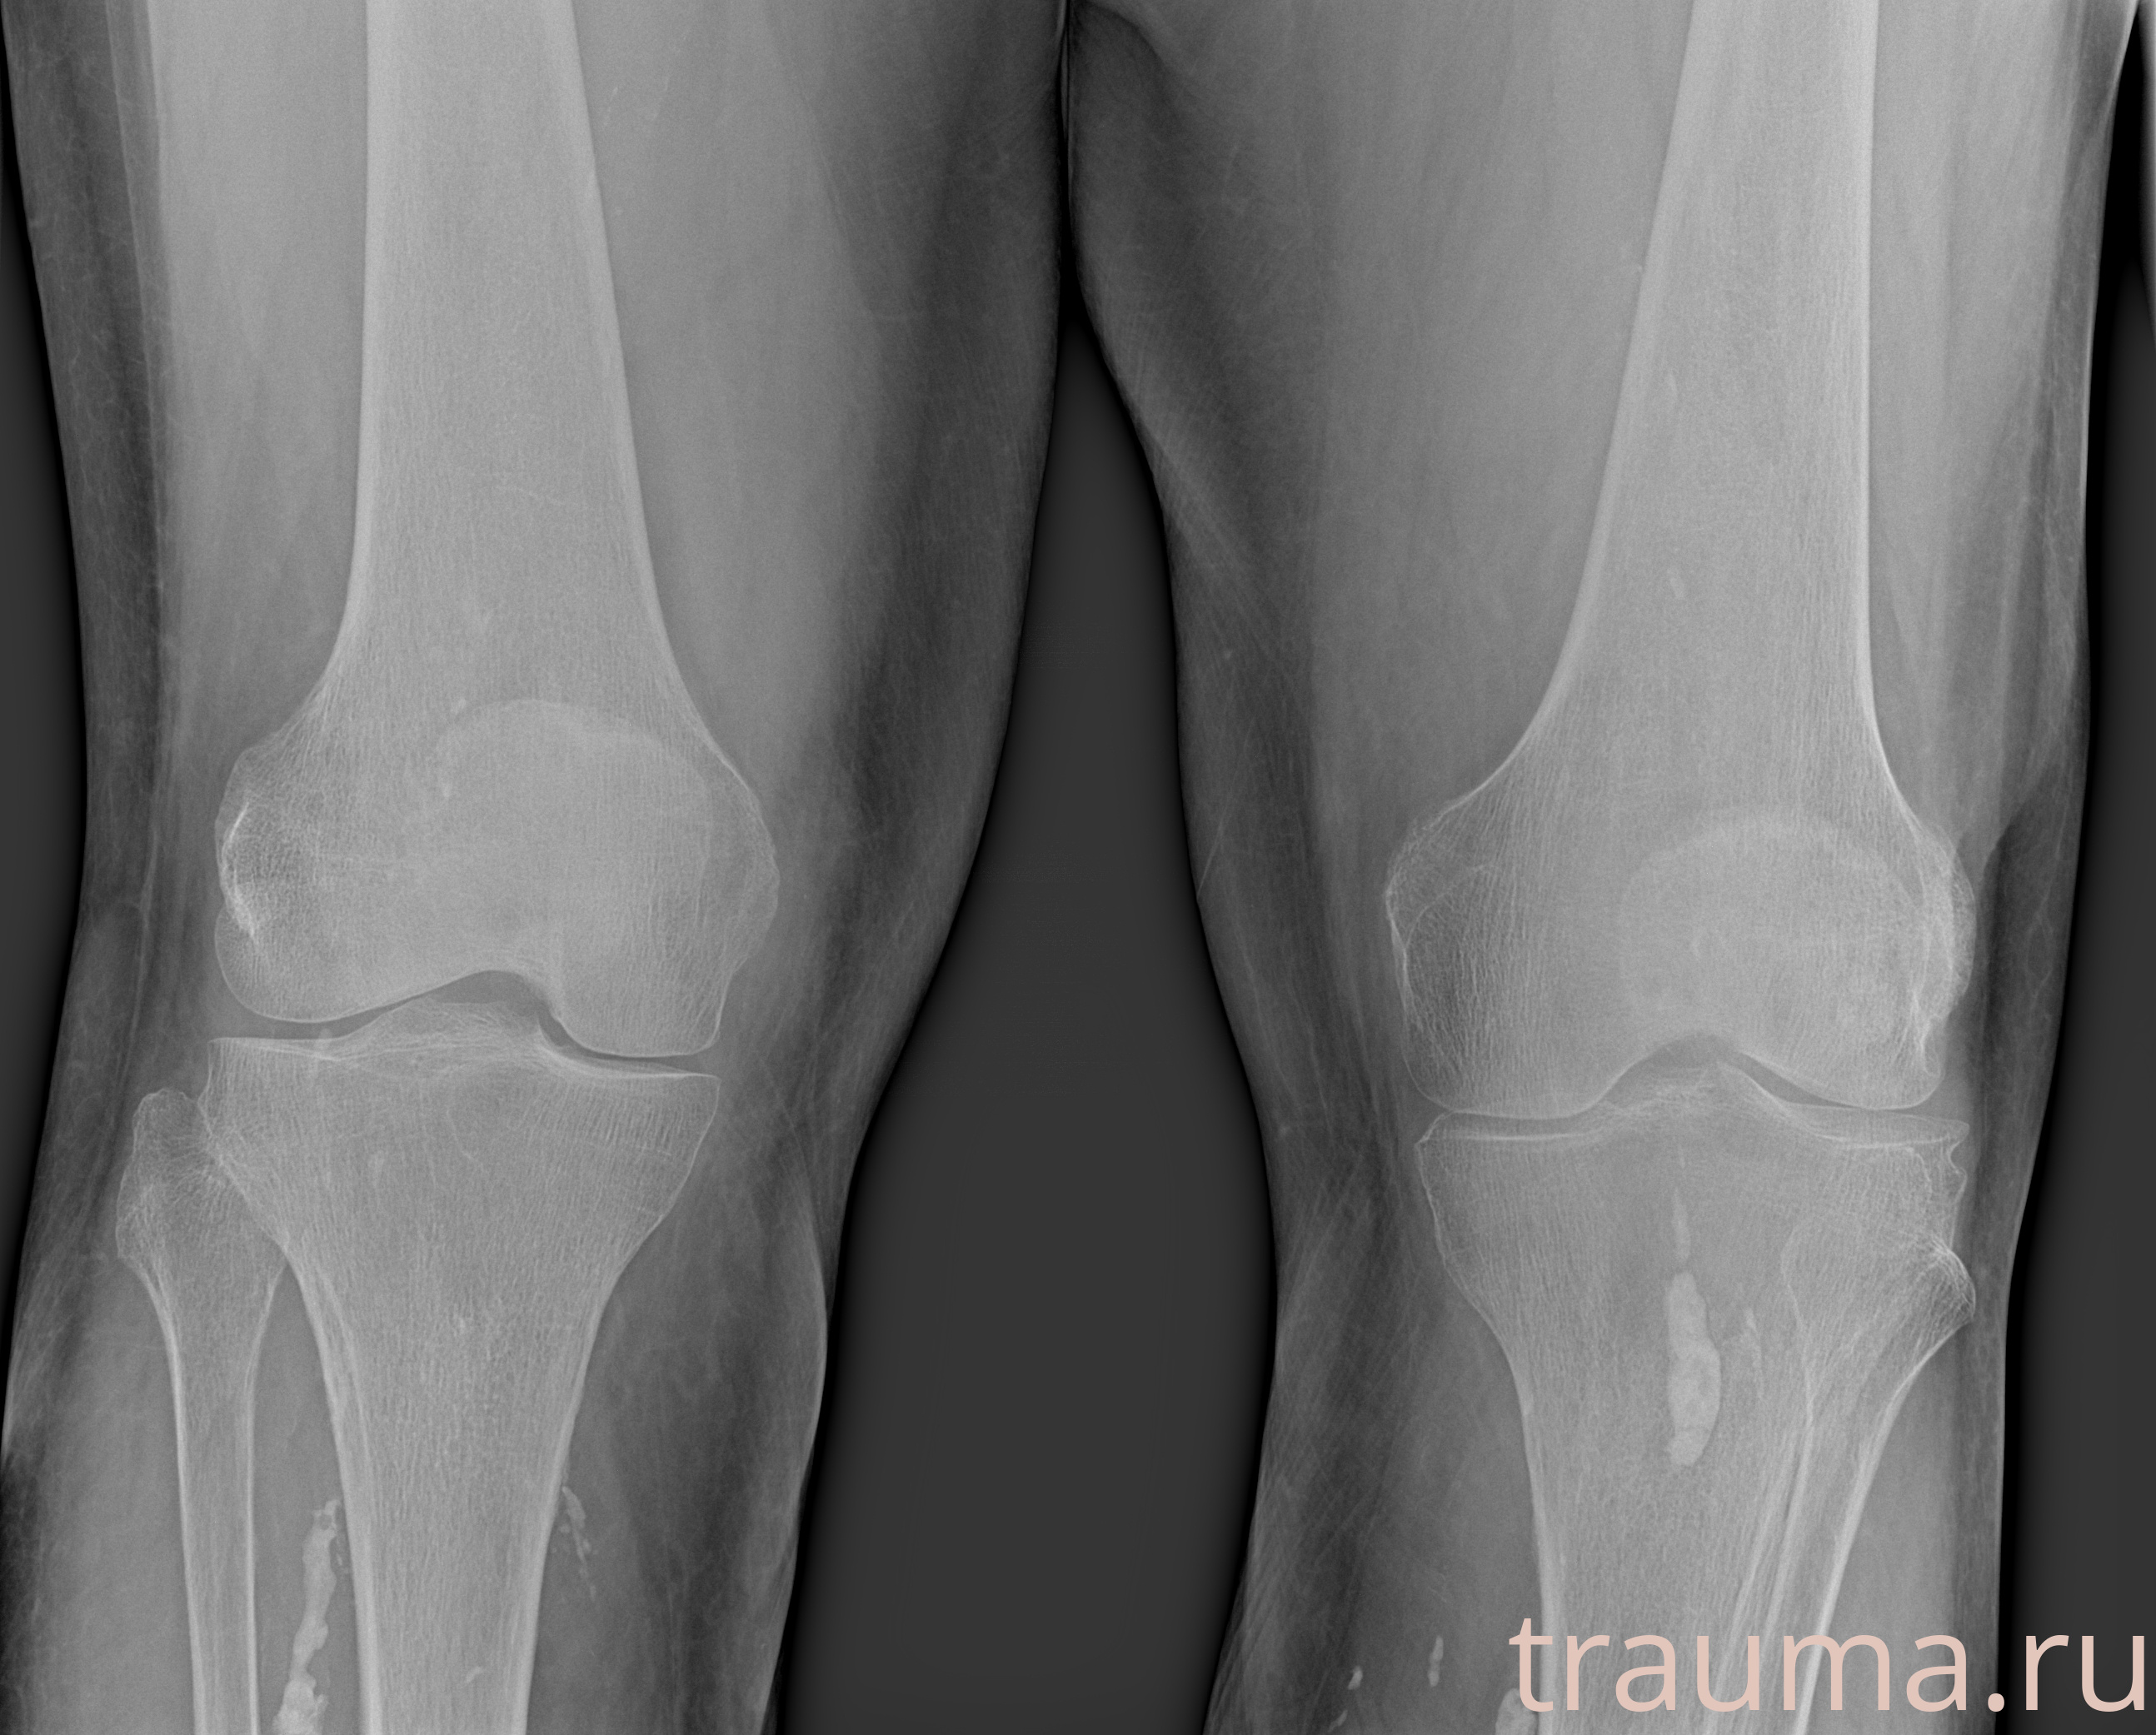

Рентгенограммы

Рентген на дому: по вашему адресу приезжает врач-рентгенолог, травматолог-ортопед с мобильным рентгеновским аппаратом, проводит диагностику травмы или заболевания, делает необходимые рентгенограммы, дает рекомендации по дальнейшему лечению. Получить качественные снимки в домашних условиях возможно благодаря уникальной методике, разработанной МосРентген Центром для института  Склифосовского